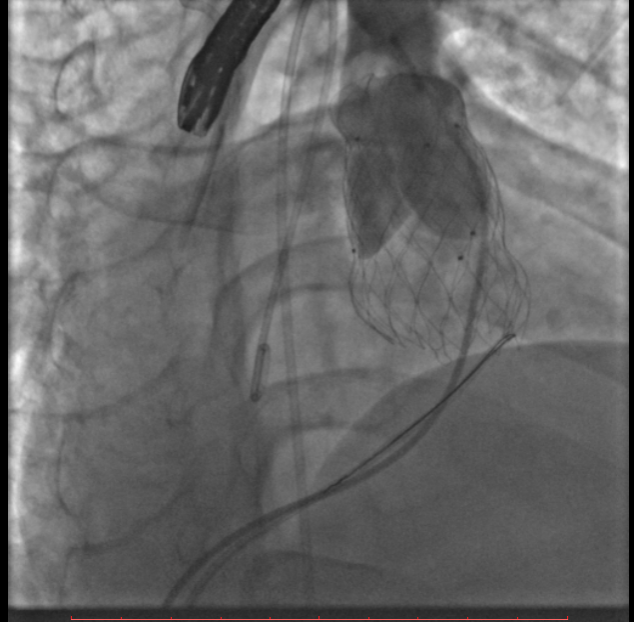

葛院士团队评估后认为,患者右肺动脉因阻挡存在狭窄,且右肺动脉与主肺动脉压差较大,具有临床意义,存在解决的必要。先后尝试Snare圈套瓣架下缘下拉法、双导管圈套瓣架上缘下拉法,但效果不理想,复测右肺动脉与主肺动脉压差仍较大,选择性右肺动脉造影仍存在右肺动脉狭窄。但考虑到患者利益,在安全操作的基础上,团队仍未放弃。拟通过将球囊送至右肺动脉开口处扩张,达到下压瓣膜支架、解除右肺动脉狭窄的效果,考虑到该操作的难点在于球囊无法顺畅到达肺瓣上目标位置,决定采用简略版PASS技术,即通过辅路送Snare至右肺动脉开口,并利用该Snare圈套住主路的Lunder quist导丝,换言之,即通过Lunder quist导丝两头发力将三尖瓣-右室流出道-右肺动脉这一扭曲的途径直线化且增强Lunder quist导丝支撑力,同时,由于Lunder quist导丝在右肺动脉处有附着力,可以避免瓣膜下移过多,如此球囊顺利通过瓣膜支架网孔进入右肺动脉,在DSA指引下逐步扩张球囊,成功使人工瓣膜支架向右心室侧移位。复查造影提示右肺动脉开口未见明显阻挡(图五),复测主肺动脉、左肺动脉、右肺动脉压力分别为32/9/19mmHg、32/7/18mmHg、29/7/17mmHg。复查肺动脉主干造影,显示人工瓣膜启闭良好,轻微瓣膜反流。最终手术疗效显著、取得令人满意的结果。

图五:通过PASS技术将球囊送至右肺动脉开口并扩张球囊、完成肺动脉瓣膜支架向心室侧移位,复查造影右肺动脉未见明显阻挡